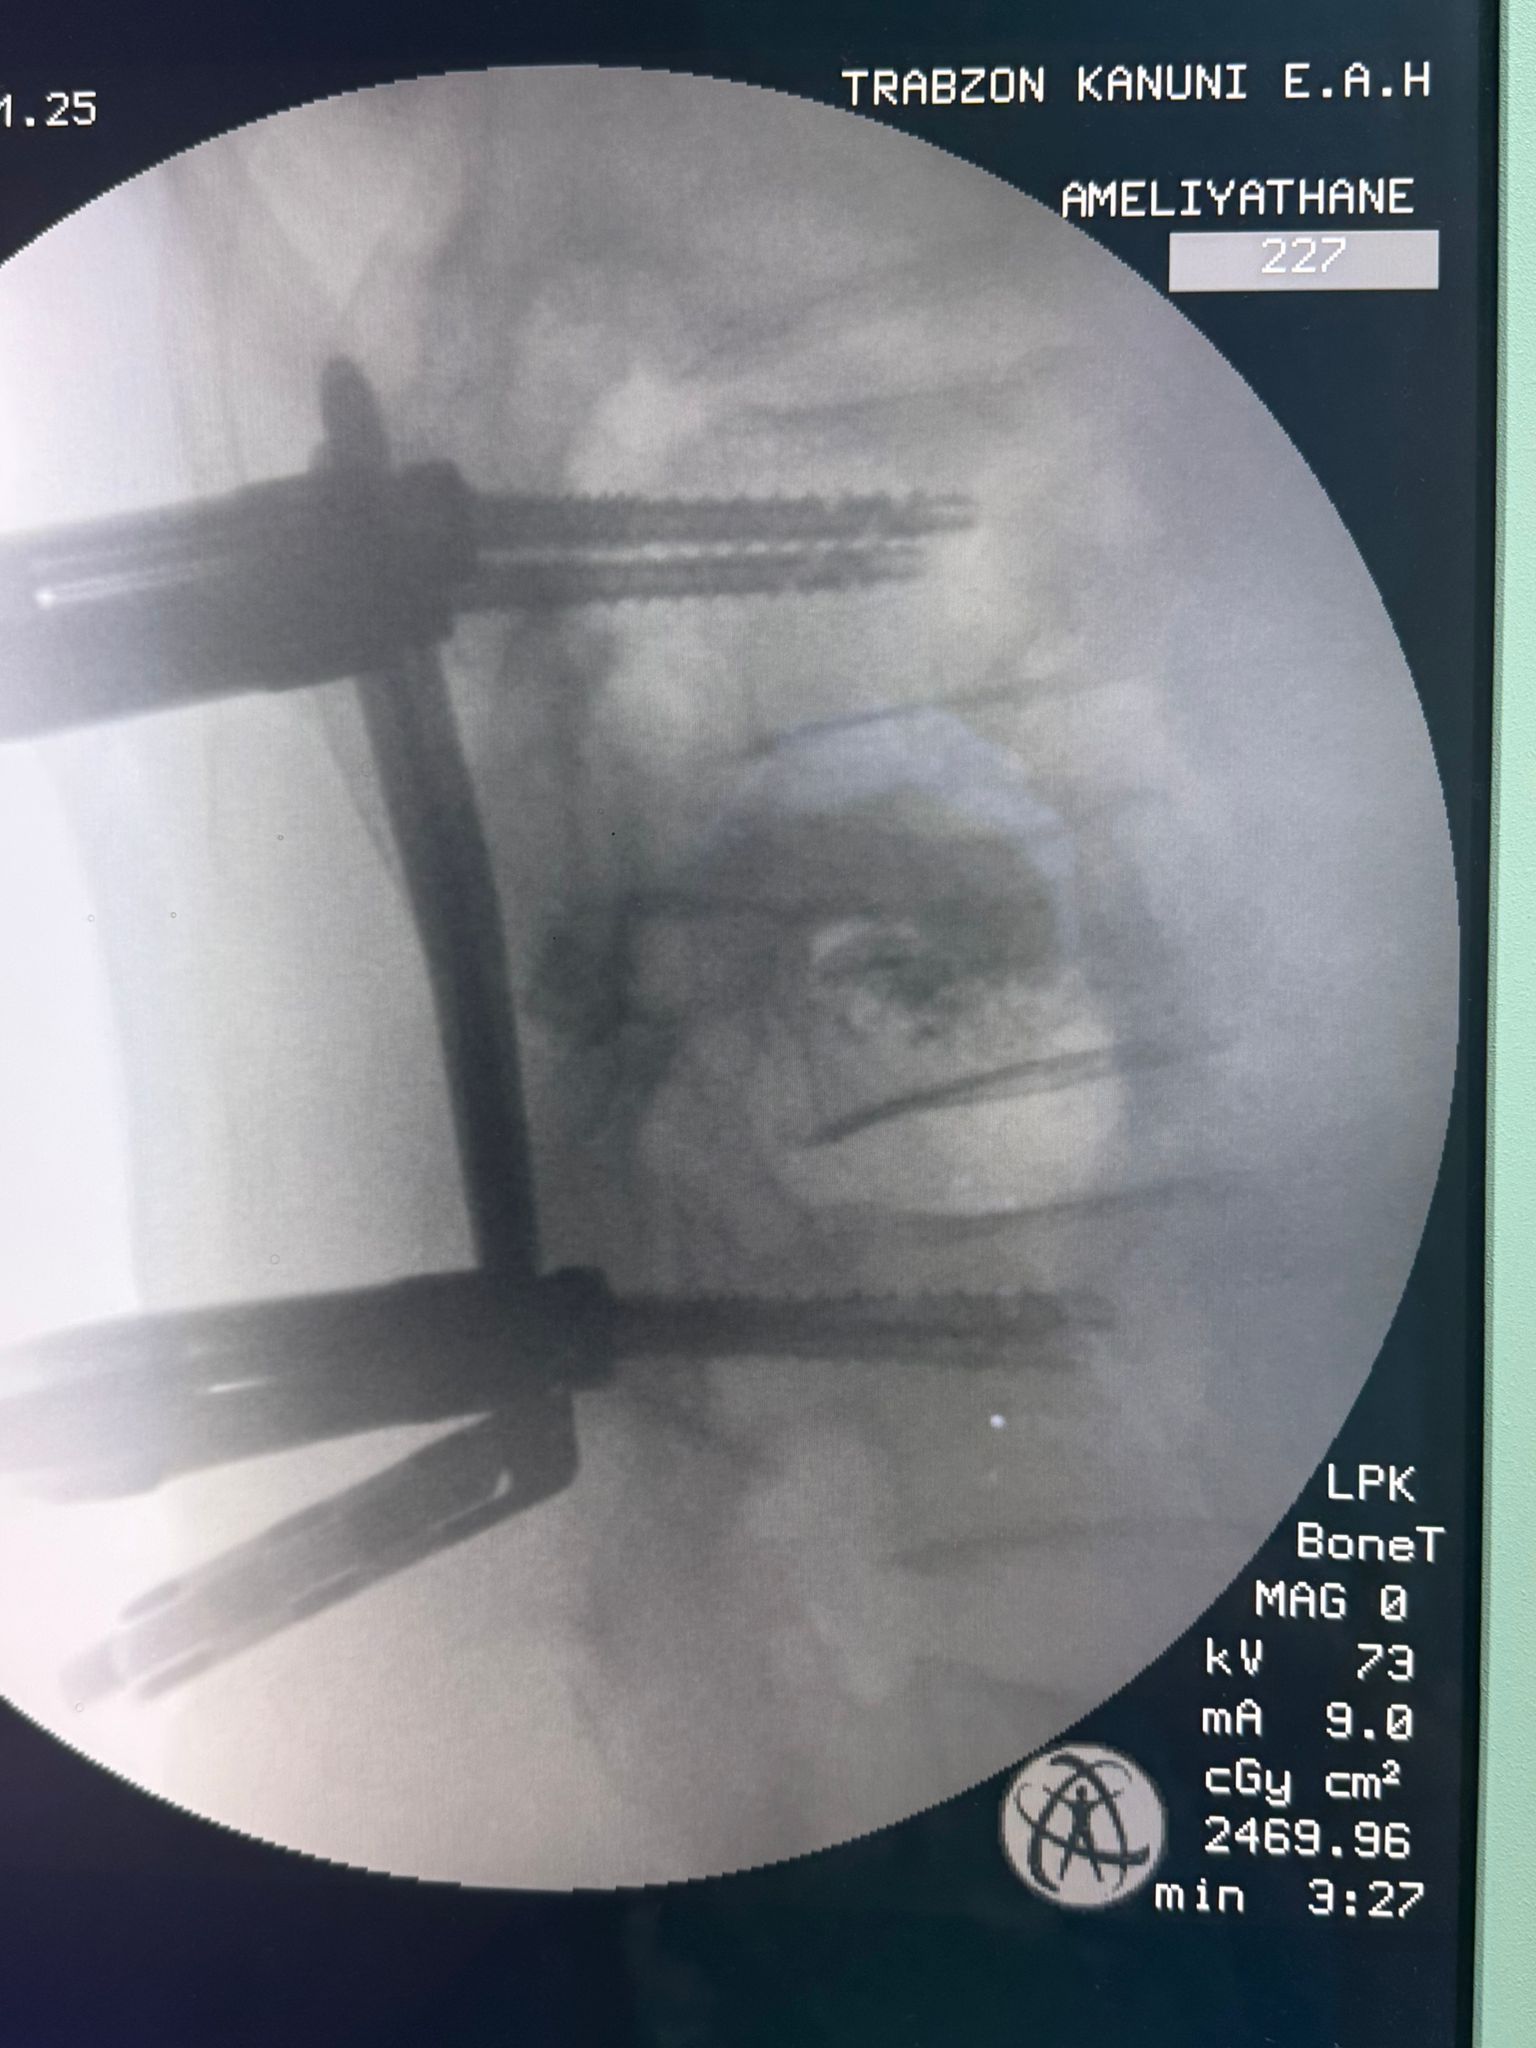

Ameliyatı gerçekleştiren Beyin ve Sinir Cerrahisi Uzmanı Dr. Gürkan Uzun ise ameliyat ile hastadaki dokuya en az zararın verilerek tedavinin mümkün hale geldiğini vurguladı.

Uzun, kesi bölgesinin çok küçük olması nedeniyle ağrı, enfeksiyon ve iyileşme gibi konularda belirgin bir avantaj sağlandığına işaret ederek, operasyon sonrası hastanın kısa sürede günlük yaşantısına dönebildiğini kaydetti.